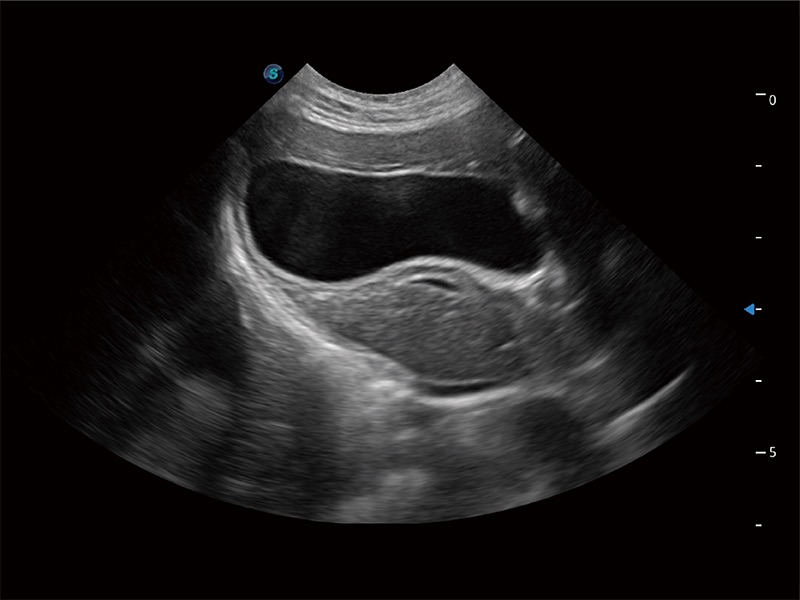

(猫)胆囊

ProPet 80 全新的动物超声智能软件和丰富的探头群,为动物医生提供了高清晰度和精细分辨率的图像,无论在宠物、马科、畜牧还是实验室动物等应用中都可以轻松应对,为您的日常工作带来满意的体验。

优异的基础图像